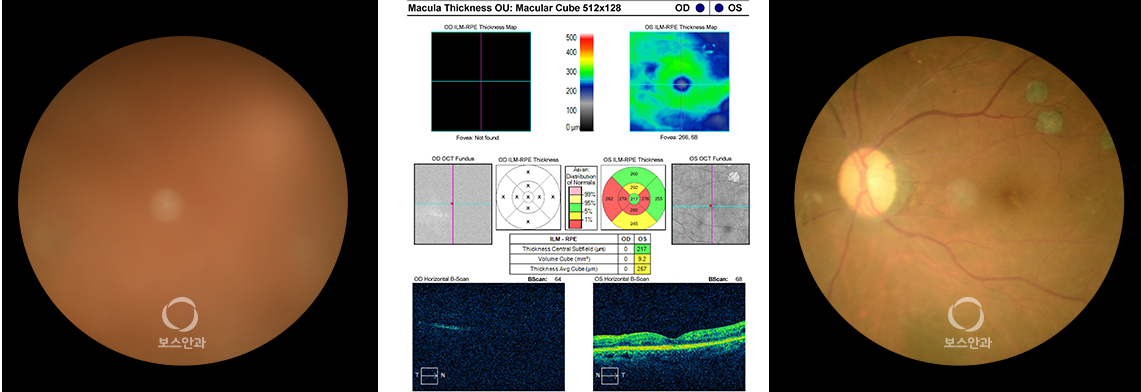

당뇨 합병증 중 가장 주의해야 하는 것이 바로 당뇨망막병증입니다.

하지만 모세 혈관벽이 약해서 물이 새어나가게 되면 황반이 붓게되어

시력 장애를 초래할 수 있습니다.

초기에는 증상이 없으므로 당뇨망막병증이 이미 생겼어도 본인은 느끼지 못할 수 있습니다.

따라서 조기진단을 위해서는 정기적으로 안과 검진을 받아야 합니다.

당뇨를 알고 있다면 증상이 없더라도 1년에 한번은 안과 검진을 받는 것을 추천합니다.